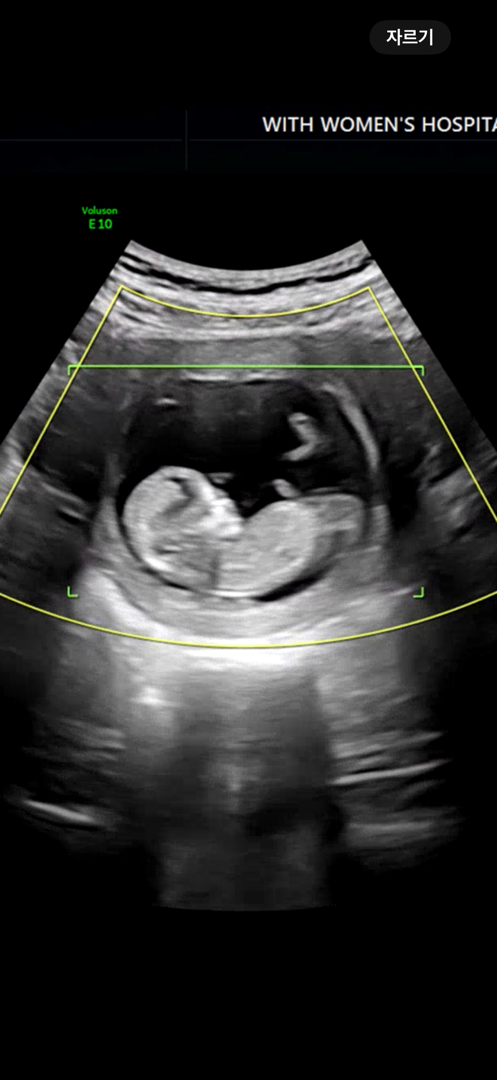

12주 각도법 한번만 봐주세요💗

아들일까요 딸일까요? ㅎㅎ 각도법 고수님들 한 번만 봐주세요.